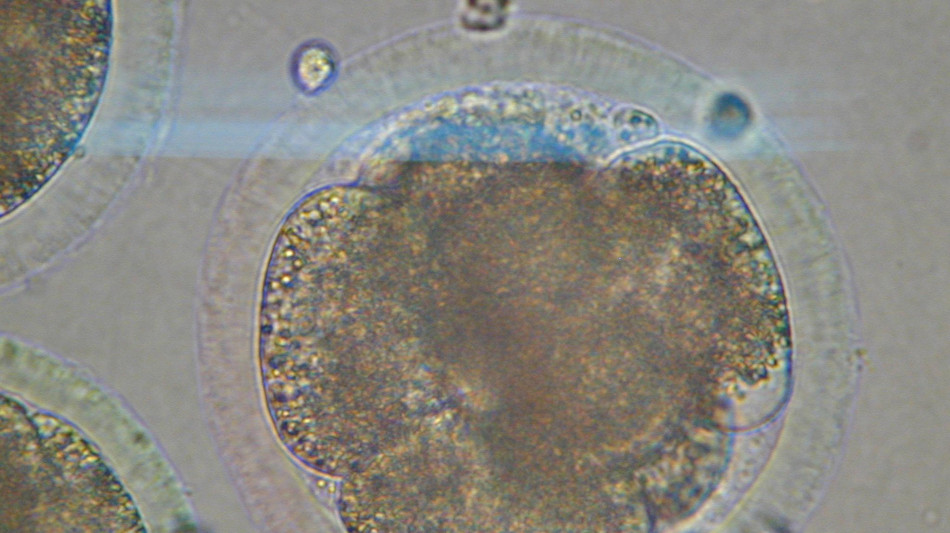

Il primo zoom sul processo di invecchiamento delle cellule indica che queste vengono rimodellate e che i cambiamenti avvengono in modo sincronizzato in ogni organo, aumentando il rischio di malattie tipiche dell'età avanzata come quelle cardiovascolari, i tumori e le demenze. E' un processo comune a tutti i mammiferi e, ora che sono stati scoperti, i segnali che lo contraddistinguono potranno diventare bersagli per future terapie. Lo indica la ricerca pubblicata sulla rivista Science e coordinata dalla Rockefeller University di New York, con il gruppo di Junyue Cao. La mappa è la prima ottenuta analizzando 7 milioni di cellule di 21 tessuti prelevati da topi giovani (un mese), di mezza età (cinque mesi) e anziani (21 mesi). Utilizzando una tecnica chiamata 'single-cell Atac-seq', in ciascuna cellula i ricercatori hanno analizzato lo stato di salute della struttura (chiamata cromatina) che impacchetta il materiale genetico per adattarlo al nucleo. E' emerso così che quando l'organismo invecchia, la composizione delle cellule e la disponibilità della cromatina cambiano in tutti i tipi di cellule e in modo particolare in quelle del sistema immunitario. Mentre queste si espandono, quelle di muscoli e reni mostrano un forte declino. "Il sistema è molto più dinamico di quanto pensassimo", afferma Cao, che ha condotto la ricerca con Ziyu Lu. "Alcuni di questi cambiamenti iniziano sorprendentemente presto" e questo, aggiunge, ci dice che "l'invecchiamento non è solo qualcosa che accade tardi nella vita, la continuazione di processi di sviluppo in corso". E' anche emerso che oltre la metà dei cambiamenti è diversa a seconda del sesso e, soprattutto, è emerso che i cambiamenti avvengono in modo coordinato tra organi distanti. "Gli stessi stati cellulari apparivano e diminuivano parallelamente in tessuti diversi. Ciò suggerisce - osserva Cao - che esistano segnali, come fattori circolanti nel sangue, che coordinano questi cambiamenti in tutto il corpo". L'obiettivo, quindi, è "capire non solo quali cambiamenti avvengono con l'invecchiamento, ma perché avvengono. Nella mappa dei cambiamenti cellulari e molecolari - osserva - possiamo identificare i fattori che guidano l'invecchiamento e questo apre le porte alla possibilità di intervenire sullo stesso processo di invecchiamento".